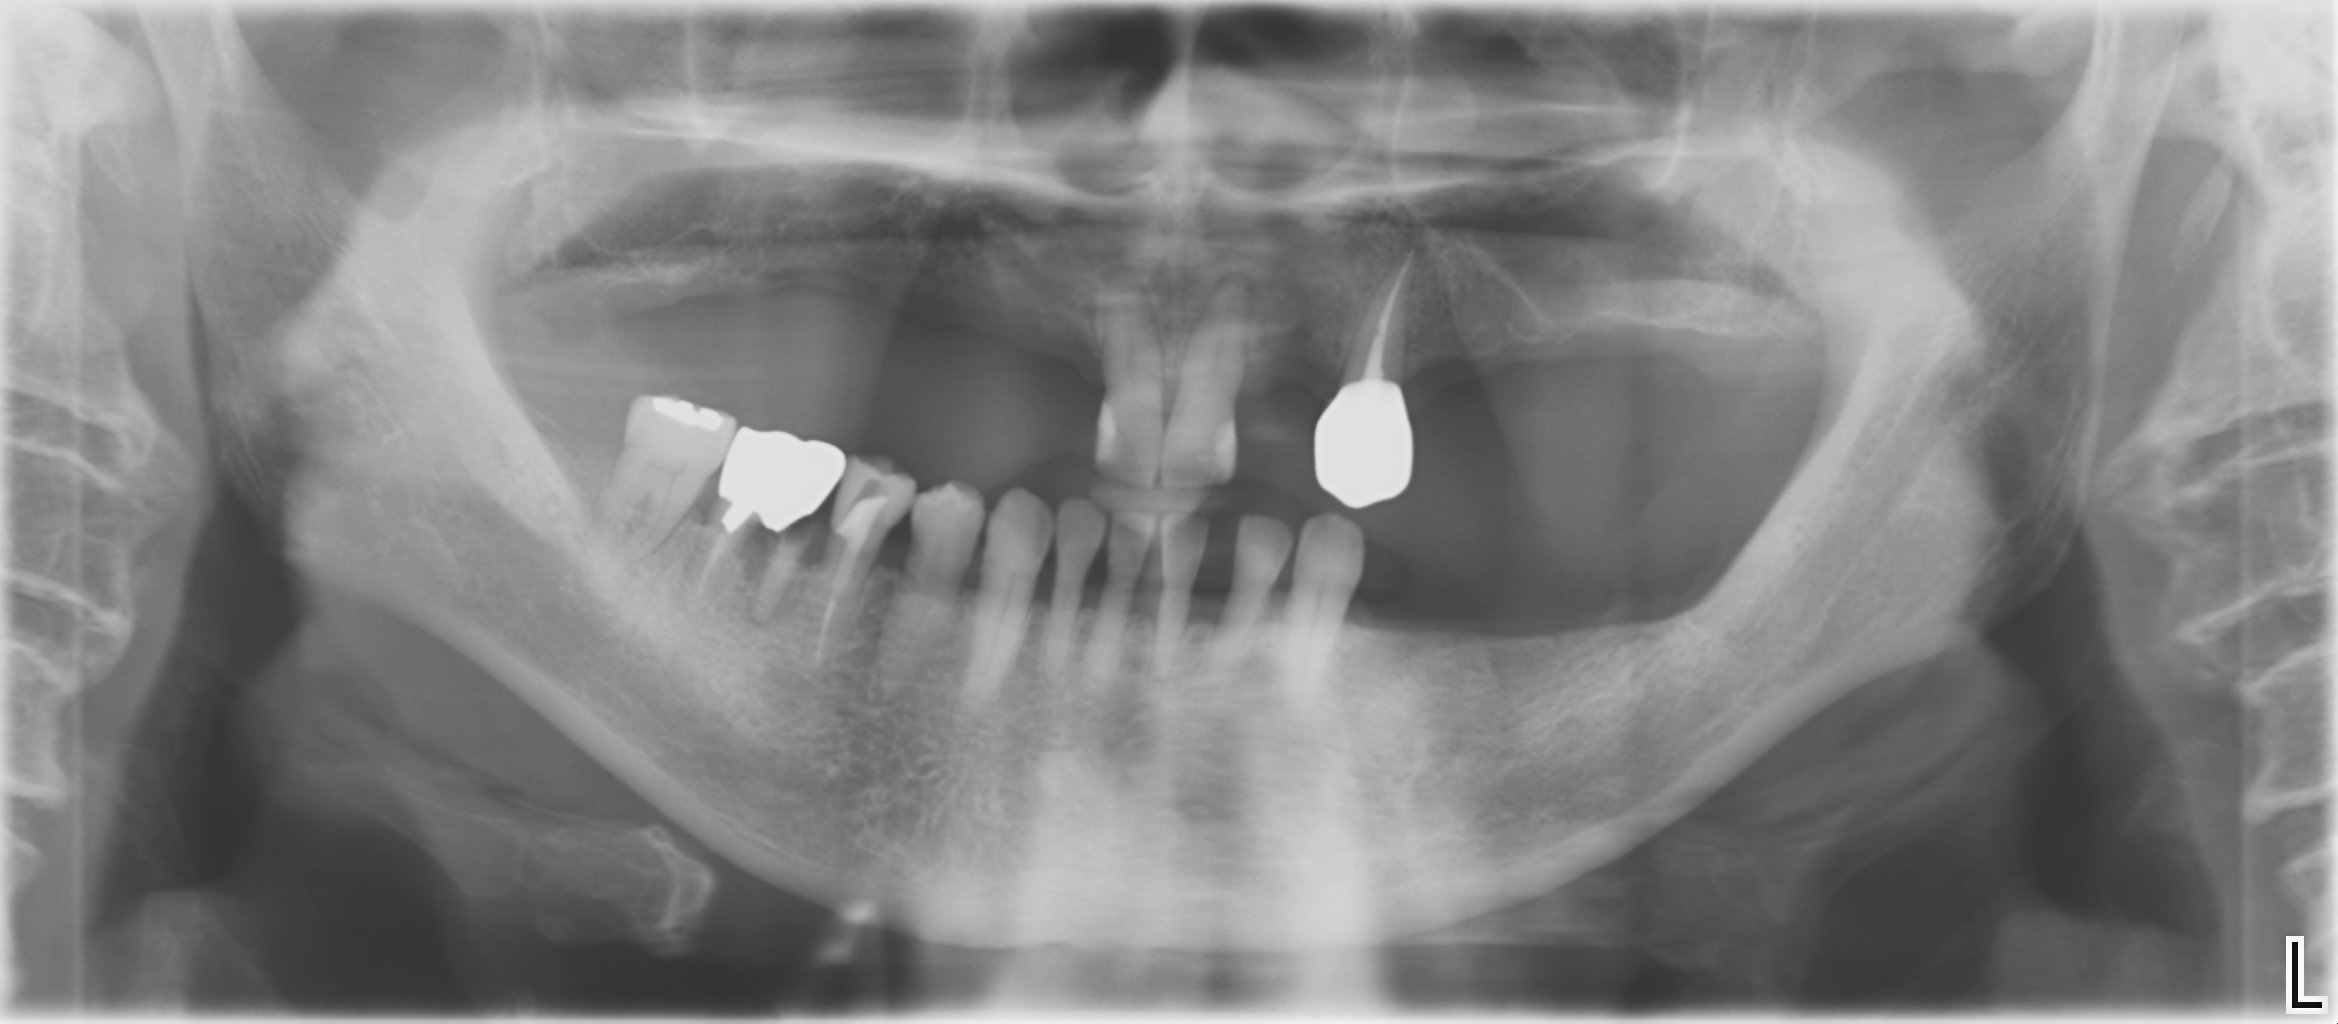

治療前写真1(パノラマX線写真)

-